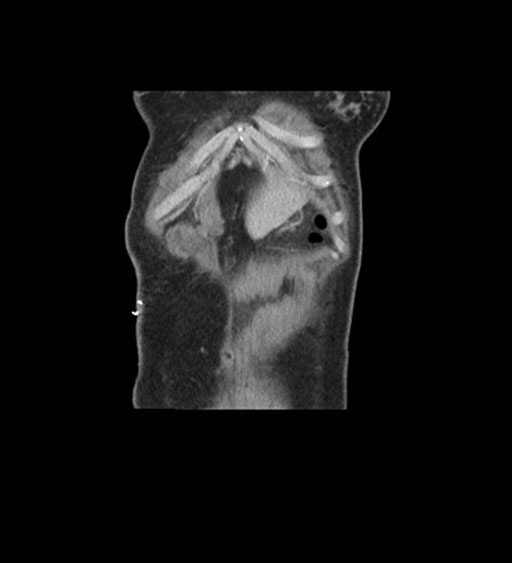

Coronal Venous